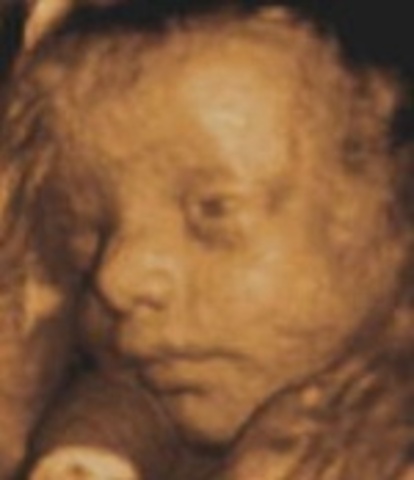

• week 19

week 19

1.placenta continues to grow and nourish the baby

2.Features baby's heart should be visible during an ultrasound

3.Scalp hair has sprouted and continues to grow.

• week 20

week 20

1.The baby can hear and recognize the mother's voice

2.The skin is getting thicker

3. The heart can now be heard with a stethoscope